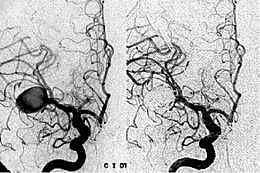

• Angiografía cerebral

Angiografía cerebral

Aproximadamente en el siglo XIX, la psicología incorporo la angiografía como un avance tecnológico y científico, la cual es una técnica que permite el análisis del flujo cerebral y la salud del sistema cerebrovascular, es una técnica en la cual se emplea los rayos x y se aplica contraste para tener una mayor visualización, esto llega a inmovilizar la cabeza.

Área de conocimiento: psicología clínica, neuropsicología imagen tomada de: https://infomedicos.tumblr.com/